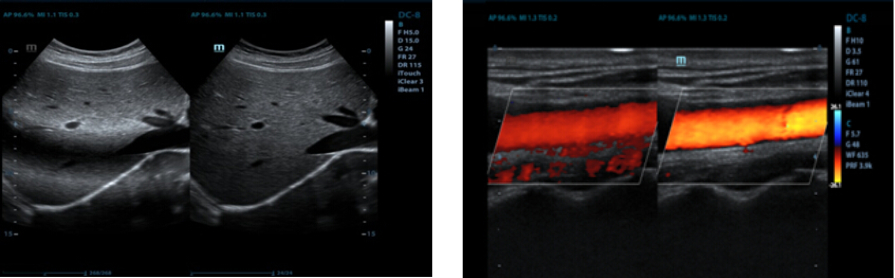

iNeedle??(Wzmocniona wizualizacja ig?y)

Funkcja ta polega na polepszeniu wizualizacji ig?y, co umo?liwia lepsz? widoczno?? ig?y, nawet podczas procedur przeprowadzanych pod ostrym k?tem z?jednoczesnym zachowaniem doskona?ej jako?ci obrazu. Dok?adniejsze potwierdzenie lokacji ig?y w?tkankach minimalizuje mo?liwo?? uszkodzenia s?siednich tkanek.

automatyczny pomiar kompleksu Intima-Media

Automatyczny pomiar grubo?ci kompleksu Intima-Media na przedniej i tylnej ?cianie naczynia, zapewniaj?cy precyzj? badania stanu t?tnicy szyjnej.

iTouch? (Automatyczna optymalizacja obrazu)

Funkcja ta umo?liwia natychmiastow?, automatyczn? optymalizacj? obrazu w trybach B, Kolorowego Dopplera i PW (spektralnego Dopplera fali pulsacyjnej) przez naci?ni?cie jednego klawisza.